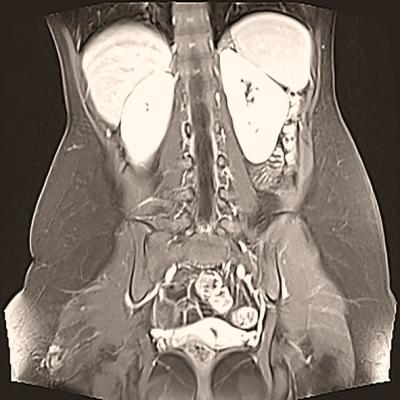

Getty Images